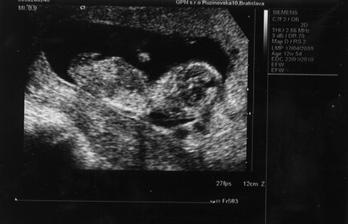

Naše krásne dievčatko